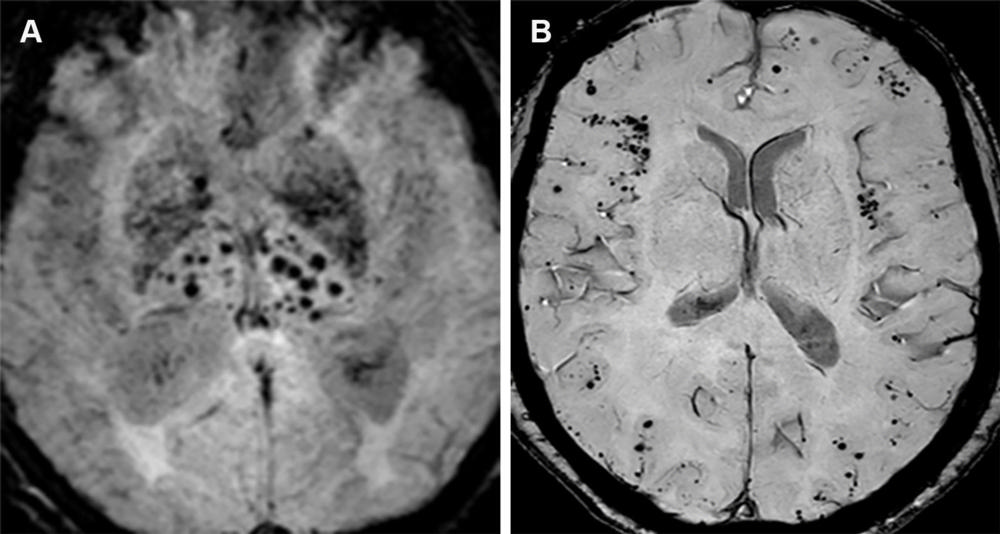

Figure 14. Advanced CAA with inflammatory changes (CAA-RI) in a 76-year-old man. (A, B) Axial susceptibility-weighted images show innumerable microhemorrhages in a peripheral lobar pattern. The patient subsequently presented to the emergency department with mental status changes, and MRI was performed. (C) Axial MR image shows cortical-subcortical edema (arrow) in the left occipital lobe consistent with acute inflammatory changes (CAA-RI). The imaging findings are indistinguishable from those of ARIA, and the differentiation is based primarily on clinical history. Moreover, patients with such a high number of microhemorrhages at pretreatment imaging are usually excluded from MAB clinical trials.

Figure 17. Hypertensive angiopathy and CAA are the two most common causes of cerebral microhemorrhages. Axial susceptibility-weighted image (A) shows a central pattern of microhemorrhages characteristic of hypertensive angiopathy, whereas on the axial susceptibility-weighted image (B), amyloid angiopathy is characterized by a peripheral/lobar pattern.